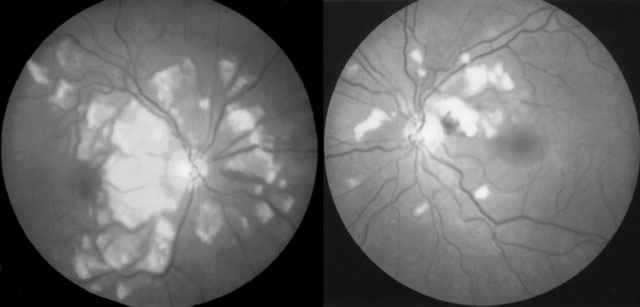

Figuras 1 y 2

EDEMA BLANQUECINO DIFUSO INTRARRETINIANO DE AMBOS POLOS POSTERIORES Y NASAL A PAPILA, MÁS MARCADO EN OD. HEMORRAGIAS RETINIANAS AISLADAS AO.